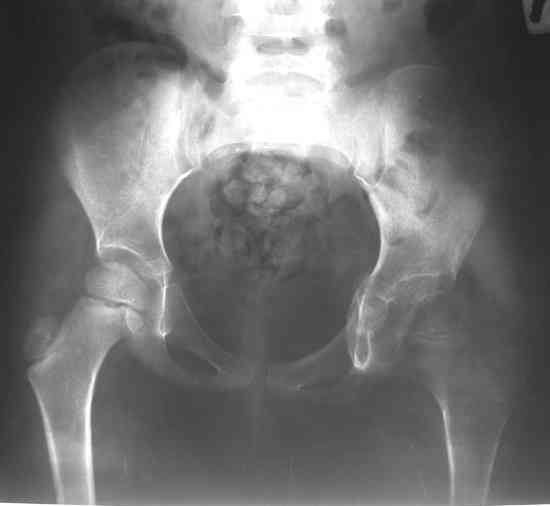

После операции ребенок находился в гонитной повязке три недели. Затем повязка снята. На контрольной рентгенограмме выявлен вывих левого бедра. Наложена система скелетного вытяжения за левое бедро. Через две недели система снята, наложена шина Веленского. Вопросы: 1. Тактика дальнейшего лечения? 2. Какое оперативное лечение оптимально предпринять? Заранее благодарю! С уважением, А.В.Владзимирский ДНИИТОDear colleagues! Female, 5 y.o. During 1 year she has pain and limitation of movements in left hip. DS: Osteochondroma of left hip. 26.07.07. surgery: arthrotomia, removing of osteochondroma, plastic of defects with “Tutoplast”, cast fixation. Cytology: parts of hyalin cartilage with sponge bone and marrow. Most possible – osteochondroma, osteochondro exostosis. Cartilage tissue not looks like typical chondroma. After 3 weeks cast fixation was removed. At x-ray – dislocation. Dislocation was treated by sceletal traction (2 weeks). Now – dislocation again. Question: Treatment? Which surgical treatment most useful in this situation? Thank you very much for your comments, opinions, ideas!!! Best wishes, Anton Vladzymyrskyy

2. Судя по представленному снимку, образование находилось внутрисуставно, а кости таза не поражены (что тогда заполнялось тутопластом? и не он ли, судя по п\о рентгенограмме явился причиной вывиха?).

А бедро надо возвращать ко впадине дистракцией, иначе в дополнение к впадине и головку угробить недолго. Видимо в дальнейшем не обойтись без пластики наружного края вертлуги.